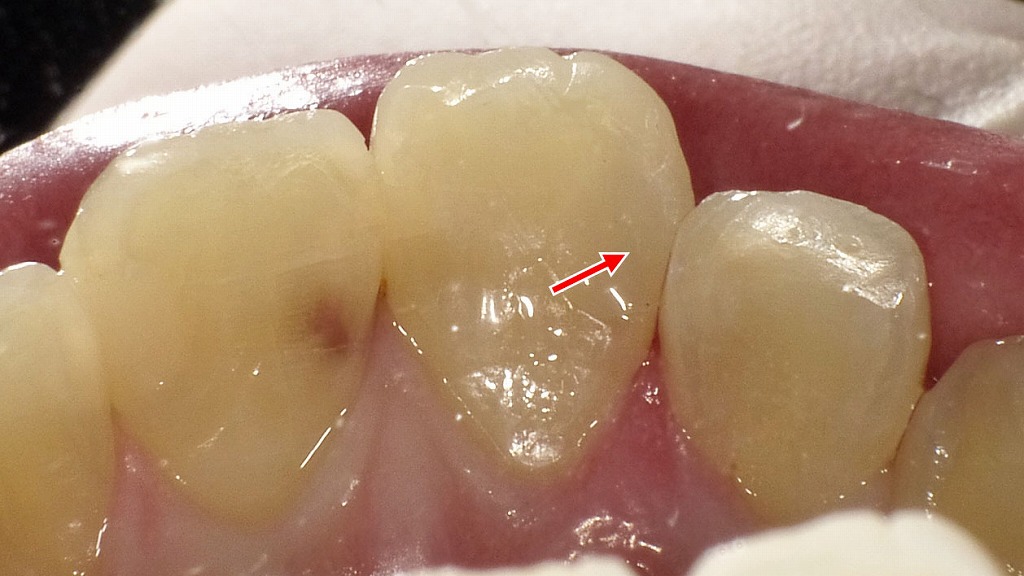

小さな穴なら…

白い樹脂(レジン)で簡単に修復できます。短時間で見た目も自然✨。

上顎1番(中切歯)に認められた、象牙質まで進行したC2虫歯の治療前後を比較した症例です。治療前はやや大きめの穴が形成されていましたが、虫歯部分を適切に除去したうえでコンポジットレジンにより修復を行いました。歯の色調や形態を考慮することで、前歯部でも自然な見た目と機能の回復が見込めます。早期治療により、歯を削る量を抑え、神経を残せる可能性が高まります。